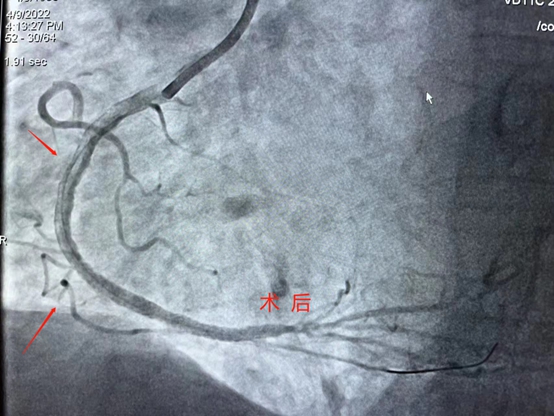

近日,商城县人民医院心血管内科首次开展血管内超声检查(IVUS)加血管内旋磨技术,这一手术治疗的完成,实现了商城县心血管疾病治疗新的突破,真正做到了大病不出县,在家门口就能享受三甲医院的治疗水平,很大程度的缓解了看病远、看病难的实际问题,造福了大别山区广大心血管疾病患者。 患者刘某,女,72岁,因有发作性胸闷、胸痛1月余并且加重3天来我院心血管内科就诊,入院后阳性检查结果示:窦心心率、频发性室性早搏、部分导联ST-T异常、左心房增大、左室壁节段性运动异常、主动脉瓣大量反流,主动脉瓣退行性变,二尖瓣少量反流,左室舒张功能减低;冠脉造影结果示:右冠状动脉重度钙化。经心血管内科熊晨晖主任团队综合评估认为常规的手术方法冠脉支架难以通过和释放,结合患者情况,经与家属沟通后,决定为其行"血管内超声+冠脉旋磨术"。 4月9日,在郑州大学第一附属医院禹海文教授的指导下,心血管内科团队成功为患者右冠脉重度钙化病变处进行了血管内超声+冠脉旋磨术后成功为患者植入了支架,手术过程顺利,术后冠脉血流恢复良好,效果满意,得到了患者及家属的赞扬与肯定! 作为国家标准化心血管诊疗中心,在这两项技术的支持下,我院心血管内科冠脉介入手术将会更加科学化、精准化,进一步提高手术成功率,全面提高我县冠脉介入水平,为复杂冠状动脉病变的患者带来福音,为全面贯彻落实《健康中国行动(2019-2030)》战略,为健康商城贡献一份力量。 科普小知识 血管内超声(intravenous ultrasound,IVUS)是指无创性的超声技术和有创性的导管技术相结合,使用末端连接有超声探针的特殊导管进行的医学成像技术。血管内超声是通过心导管将微型化的超声换能器置入心血管腔内,显示心血管断面形态和(或)血流图形,主要包括超声显像技术和多普勒血流测定两方面。这种技术使得超声技术,如压电传导或者超声传感器得以用于检查血管内壁的情况。 血管内超声主要应用于冠状动脉系统的诊断。1.冠状动脉造影不能明确诊断的病例。2.需明确病变形态和斑块性质。3.评价病变长度,明确支架的选择和放置。4.评价支架植入术等冠状动脉介入治疗疗效。5.冠状动脉病变的远期随访性研究。 什么是冠脉旋磨术? 冠状动脉内膜旋磨术(coronary trartsluminal rotational atherectomy,Rotablator),或称为冠脉旋磨成形术(简称旋磨术),是指使用带有超高速旋转的转头Rotablator将冠脉内粥样硬化斑块、钙化组织碾磨成极细的微粒,从而将阻塞的血管腔的斑块消除。 冠脉旋磨术的适应症 冠状动脉腔内斑块旋磨术主要适用于解剖学上高危的病变,如钙化的病灶、开口处病灶、球囊难以扩张的病灶和长段血管病灶。从冠脉病变分型来看,这些病变多属C型病变,PTCA功率低且并发症发生率较高,但不少报道显示采用旋磨术治疗早期手术成功率很高,而并发症的发生率却明显减少。 冠脉旋磨术的手术方法 先经股动脉硝插入一根8~10F标准导引管至冠状动脉口,然后经导引管送入旋磨导管,将特制的导丝送过狭窄病变至冠状动脉远端,再沿导丝将钻磨头推送至狭窄病变的近端,开动马达使钻磨头高速旋转并推动其前进直到通过病变,最后关闭马达。钻磨头可后撤至病变近端,重复旋磨直到推送和后撤钻磨头时阻力消失,术后重复造影满意,撤出钻磨头。如结果不满意时,可辅以PTCA,以扩张残余狭窄。